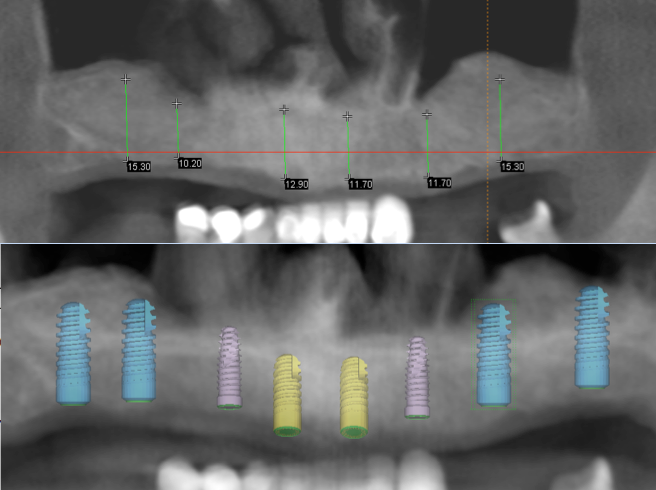

Often a fixed bridge is placed on four implants; this is often called an “All on Four”. In practice we would recommend that six implants will provide a better platform than four implants.

The advantages of six implants

- With six implants, each implant will bear less load

- The balance of weight distribution is improved

If at a later date you were to have a problem with a six implant supported bridge (which would be less likely than with a four implant bridge), you will still have five implants which is adequate support to continue. If you have a four unit bridge and lost one implant, the remaining three would be insufficient to carry the load and the bridge would fail.